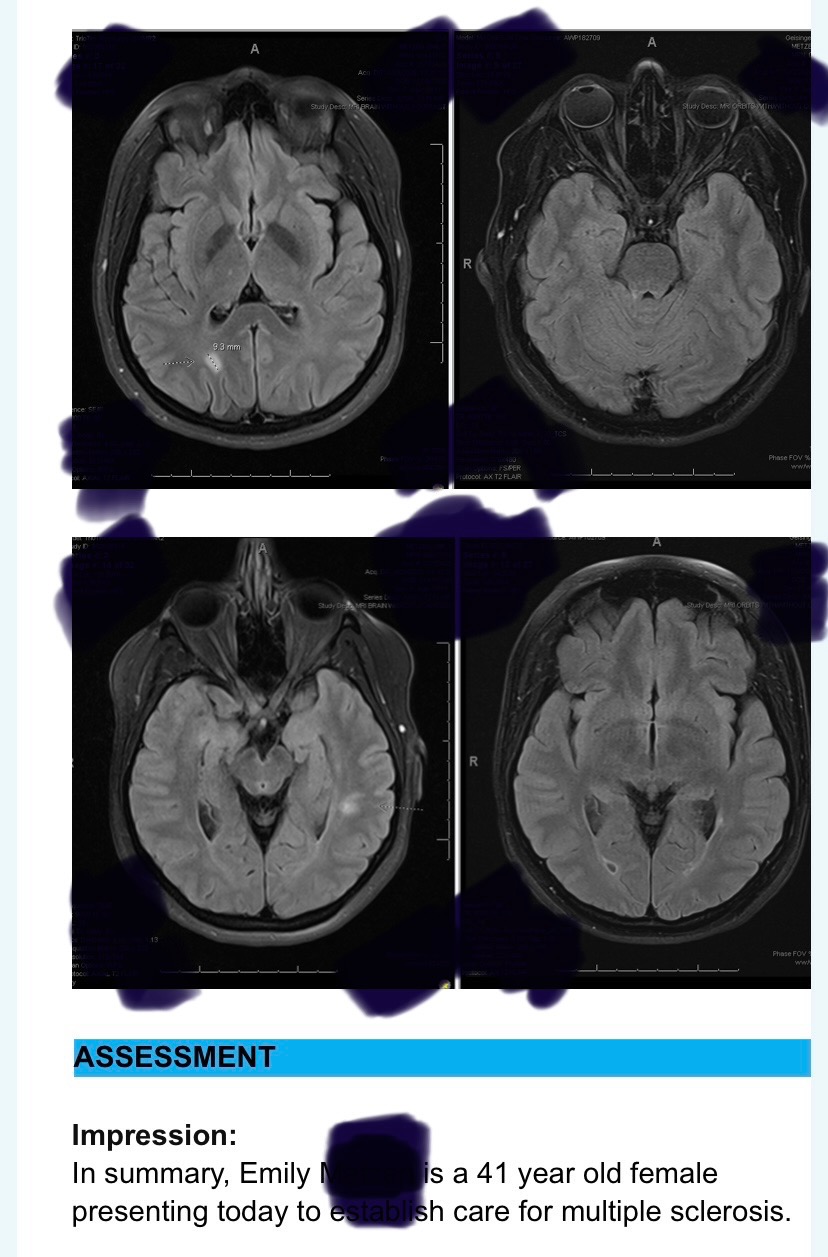

Hello, my name is Emily and I make ASMR content and I do live streams daily. I have multiple sclerosis, Mast cell activation disorder as well as alpha gal syndrome. With having all these conditions it makes it very difficult for me to find medication to help me. I suspect I have had MS since I was 21 years old. I had one brain lesion, but they could not give me a diagnosis at the time so I went years with no treatment. In 2013 I was diagnosed with Alpha gal syndrome from a tick bite, in 2017, I developed another tick bite and I started reacting to more things and foods. I suspect I developed mast cell activation disorder at that time. I was not diagnosed with mast cell disorder until 2025. In 2025 I was diagnosed also with multiple sclerosis due to having optic neuritis. I was admitted to the hospital where they found multiple lesions on my brain and spine.

I have had about five MRIs since then and it shows I have been having constant relapses with no remission. Back in April, they sent me to have steroid infusions and I started reacting to the prednisone. They now list it as an allergy. Within a year, I have declined significantly you may not see that by looking at me, but I can feel it, and it shows on all my tests.